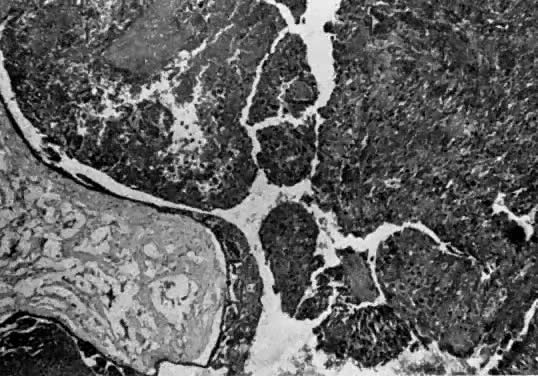

Partial Hydatidiform Mole

As discussed subsequently, the cytogenics of complete and partial hydatidiform moles have established that partial hydatidiform moles are usually derived from a triploid conceptus whose placenta is characterized by focal, variable hydropic villi and usually by focal, slight trophoblastic hyperplasia.24,25,26,29 Other histologic features include scalloping of the villi by trophoblastic inclusions within chorionic villi. The embryo survives much longer than in complete moles, with embryonic deaths typically occurring at or before approximately 8 weeks of gestational age. Frequently there is macroscopic or microscopic evidence of a fetus (Fig. 8).24,25,26,29 Fetal vessels are most often identified and usually contain nucleated fetal erythrocytes. The histologic features may vary, depending on the gestational age of evacuation of a partial hydatidiform mole. Hydropic change progresses in severity throughout gestation. Because of the focal nature of the hydropic changes and trophoblastic proliferation, multiple tissue sections must often be obtained to make the diagnosis of partial hydatidiform mole.

Fig. 8. Microscopic view of partial hydatidiform mole. Top. At the upper edge is a large central cistern. Smaller villi show edema and various degrees of scalloping. The fetus was alive. Trophoblastic hyperplasia was inconspicuous but present. Bottom. The wall of a large cistern formed in the presence of a functioning fetoplacental circulation. Note patent, well-formed villous vessels filled with fetal erythrocytes.(Sulzman A, Buchsbaum HJ: Gestational trophoblastic disease. In Clinical Perspectives in Obstetrics and Gynecology, p. 38. New York, Springer-Verlag, 1987.